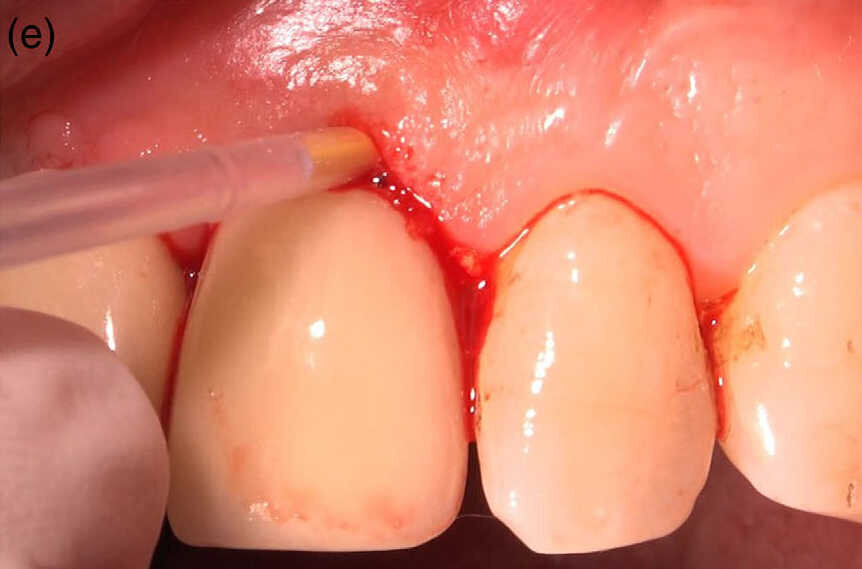

Fig 1 (e) Injection de 1 mg de microsphères de chlorhydrate de minocycline dans le sillon gingivo-dentaire.